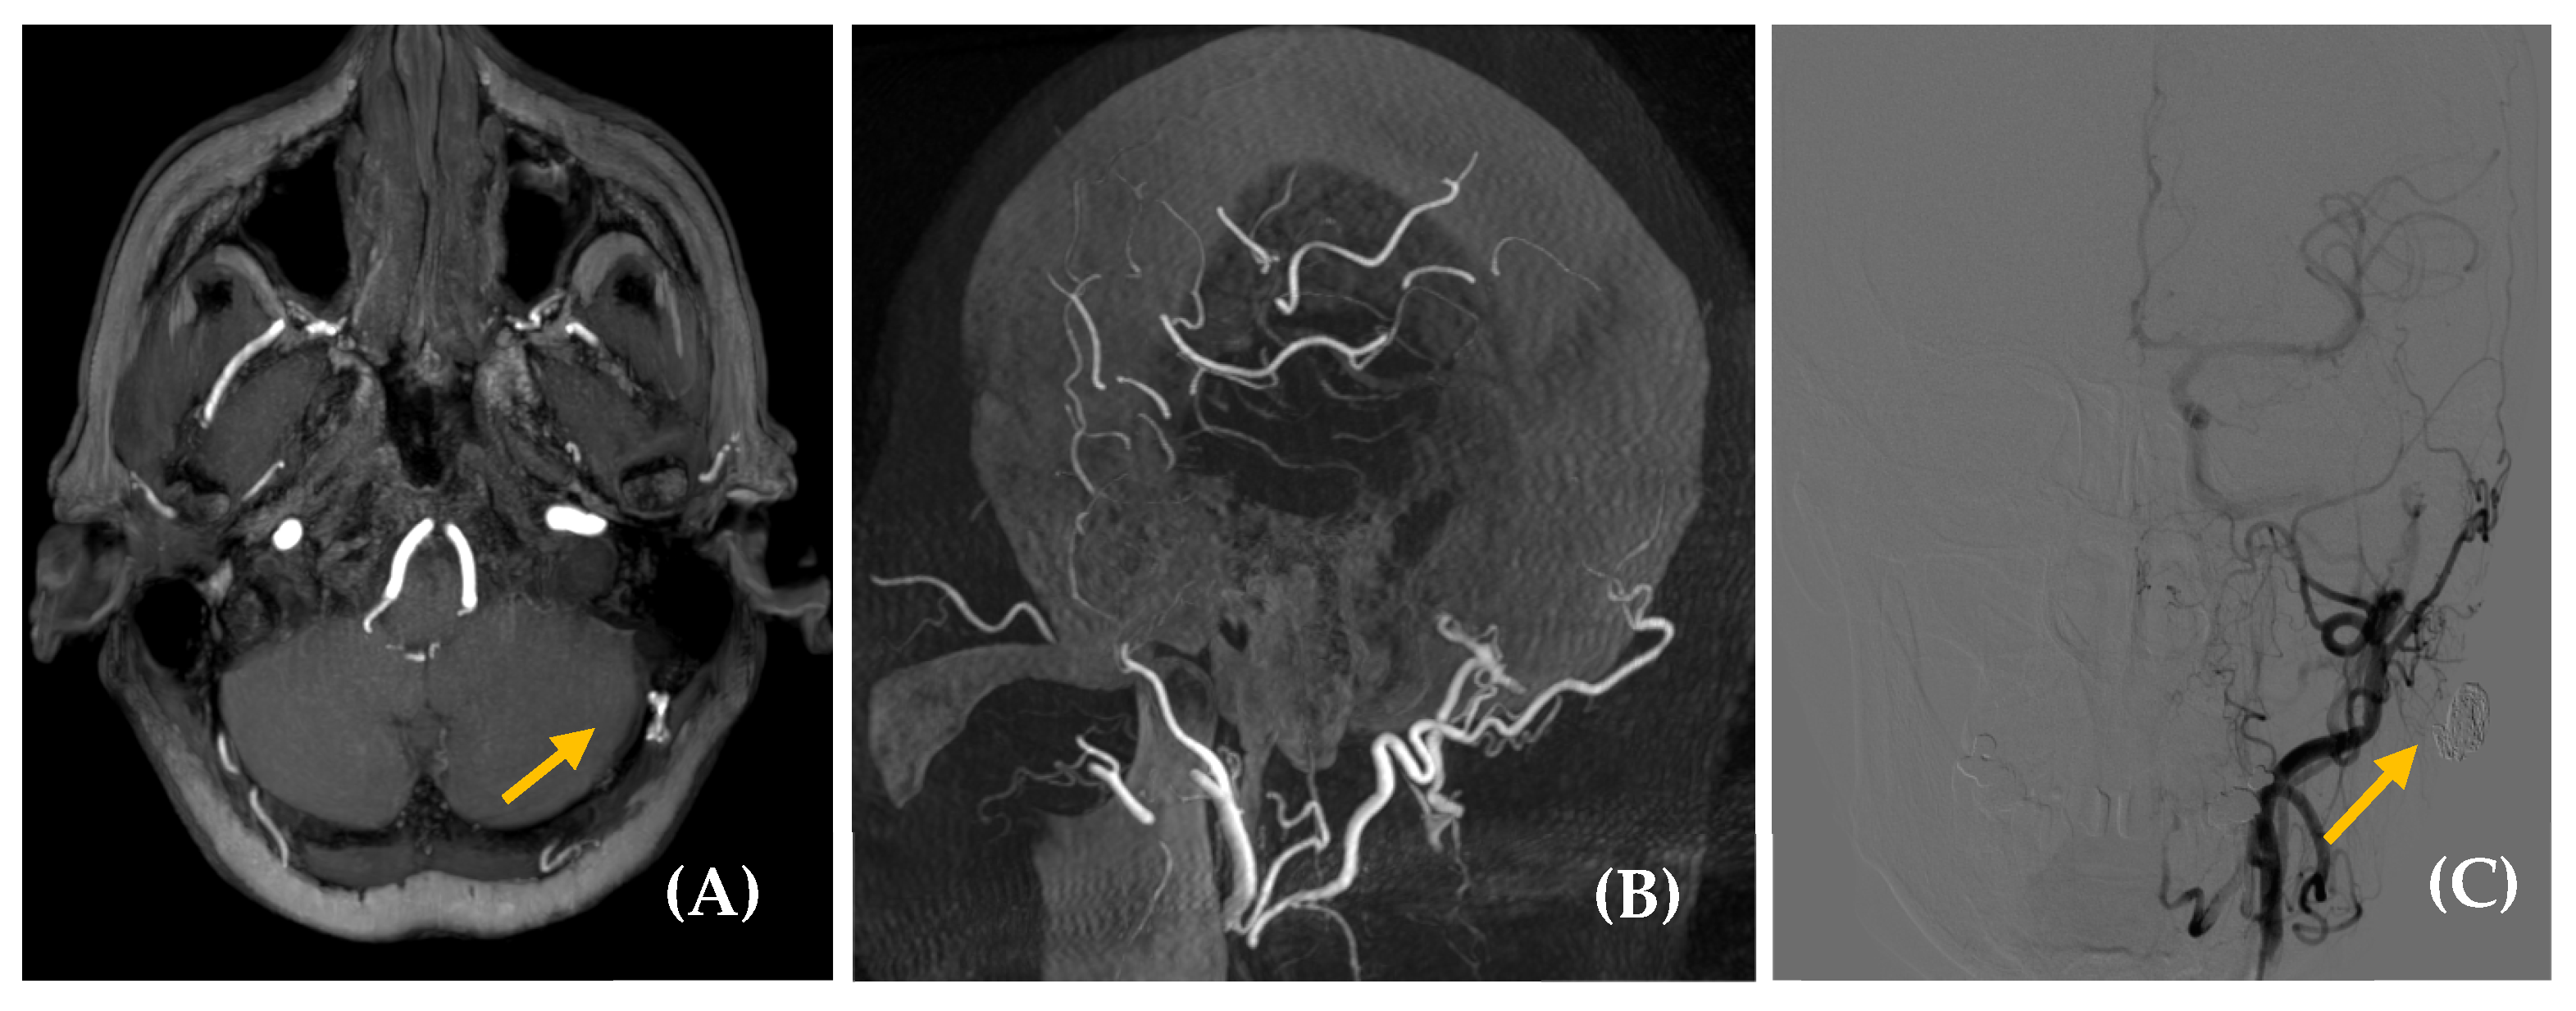

- Gandhi, D.; Chen, J.; Pearl, M.; Huang, J.; Gemmete, J.J.; Kathuria, S. Intracranial dural arteriovenous fistulas: Classification, imaging findings, and treatment. AJNR Am. J. Neuroradiol. 2012, 33, 1007–1013. [Google Scholar] [CrossRef]

- Miller, T.R.; Gandhi, D. Intracranial dural arteriovenous fistulae: Clinical presentation and management strategies. Stroke 2015, 46, 2017–2025. [Google Scholar] [CrossRef]

- Serulle, Y.; Miller, T.R.; Gandhi, D. Dural arteriovenous fistulae: Imaging and Management. Neuroimaging Clin. N. Am. 2016, 26, 247–258. [Google Scholar] [CrossRef]

- Elhammady, M.S.; Ambekar, S.; Heros, R.C. Epidemiology, clinical presentation, diagnostic evaluation, and prognosis of cerebral dural arteriovenous fistulas. Handb. Clin. Neurol. 2017, 143, 99–105. [Google Scholar] [CrossRef]

- Zipfel, G.J.; Shah, M.N.; Refai, D.; Dacey, R.G., Jr.; Derdeyn, C.P. Cranial dural arteriovenous fistulas: Modification of angiographic classification scales based on new natural history data. Neurosurg. Focus 2009, 26, E14. [Google Scholar] [CrossRef] [PubMed]